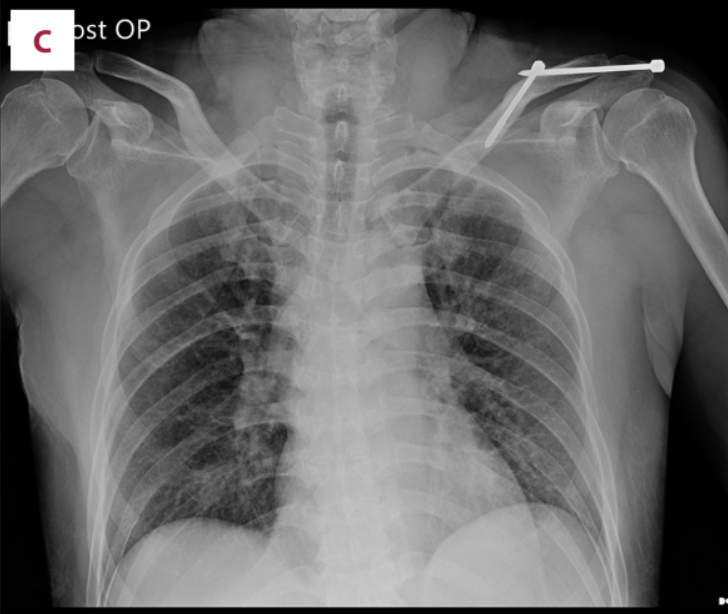

术后立即肩部x线片显示,锁骨骨折切开复位和Knowles针内固定后,肩锁关节(ACJ)明显移位。根据Rockwood分型诊断为V型ACJ脱位

(A)在c臂图像增强器的帮助下,用克氏针将锁骨推入解剖位置进行闭合复位。(B)从肩峰尖端穿过肩锁关节(ACJ)至锁骨远端,用Knowles钉在锁骨远端后侧实现皮质锚定。采用Knowles销固定时,采用拉力螺钉技术保持ACJ空间。(C)术后x线片显示经皮Knowles针闭合复位治疗ACJ脱位复位良好。